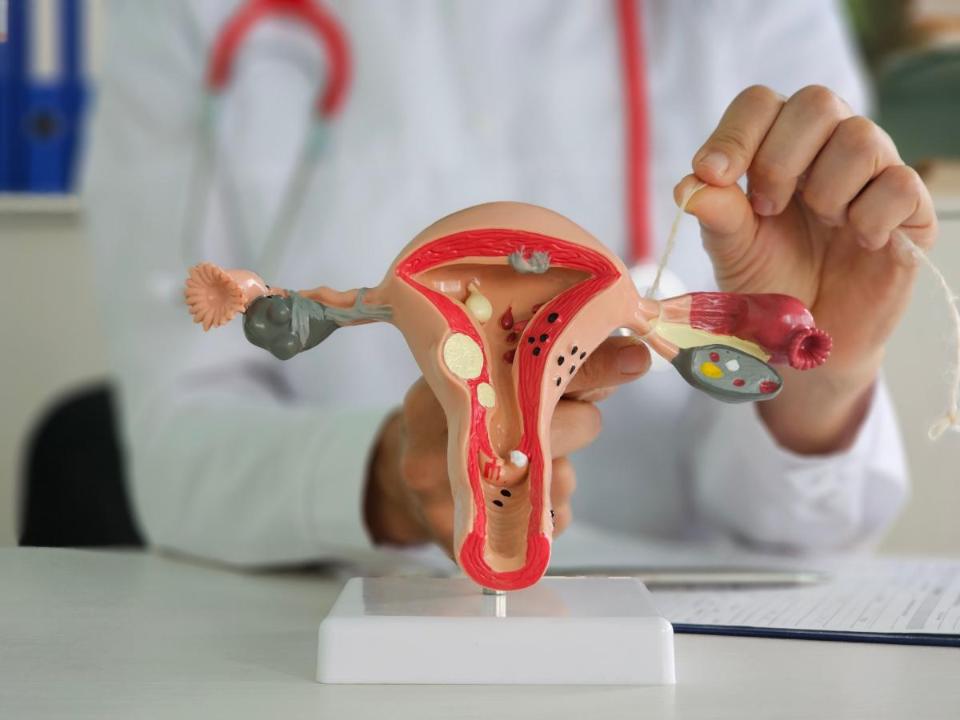

Qadın sağlamlığını qorumaq üçün vacib olan ginekoloji əməliyyatlar haqqında ətraflı məlumat əldə edin. Vaginaplastika, labioplastika, hudoplastika, təbii doğuş, qeysəriyyə, sonsuzluğun müalicəsi və vaginizmin müalicəsi mövzularında peşəkar məsləhətlər və müasir yanaşmalarla tanış olun. Sağlamlığınıza yatırım edin!

Qadın sağlamlığı və genital estetika ilə bağlı məqalələr

Ginekoloji Əməliyyatlar Haqqında Ən Çox Verilən Suallar

Vaginaplastika nədir?

Vaginaplastika vaginal kanalda və ətrafında struktur dəyişikləri düzəltmək məqsədilə həyata keçirilən cərrahi bir əməliyyatdır. Bu əməliyyat, doğum sonrası dəyişikliklər və ya hormonal dəyişikliklər nəticəsində meydana gələn narahatlıqları azaltmağa kömək edir.

Labioplastika nə üçün edilir?

Labioplastika, genital bölgənin görünüşünü və funksionallığını yaxşılaşdırmaq məqsədilə labia minor (kiçik dodaqlar) və ya labia major (böyük dodaqlar) üzərində edilən əməliyyatlardır. Bu əməliyyat, qadınların öz bədənlərinə olan inamını artırır və rahatlığını təmin edir.

Hudoplastika nədir?

Hudoplastika, klitoral örtüyü (clitoral hood) düzəltmək və ya azaltmaq məqsədilə həyata keçirilən bir cərrahi müdaxilədır. Bu əməliyyat, genital bölgənin estetik görünüşünü yaxşılaşdırmağa kömək edir.

Təbii doğuş və qeysəriyyə arasında hansı fərqlər var?

Təbii doğuş vaginal yolla doğumun həyata keçirilməsidir, qeysəriyyə isə cərrahi müdaxilə ilə körpənin ana bətnindən çıxarılmasıdır. Hər iki yanaşmanın öz üstünlükləri və riskləri var, buna görə həkimlə müzakirə etmək vacibdir.

Sonsuzluğun müalicəsi necə aparılır?

Sonsuzluğun müalicəsi, fərdin xüsusi ehtiyaclarına və səbəblərinə görə dəyişir. Müalicə metodları arasında hormonal terapiya, cərrahi müdaxilələr, in vitro fertilizasiya (IVF) və digər müasir üsullar yer alır.

Vaginizm nədir və necə müalicə edilir?

Vaginizm vaginal əzələlərin involuntary şəkildə sıxılaraq penetrasiyaya mane olmasıdır. Müalicə, terapevtik yanaşmalar, fiziki müalicə və bəzən cərrahi müdaxilə ilə həyata keçirilir.

Açıq/qapalı ginekoloji əməliyyatlar arasındakı fərqlər nələrdir?

Açıq əməliyyat geniş bir kəsiklə həyata keçirilir, qapalı əməliyyat (laparoskopiya) isə kiçik kəsiklərdən daxil olunaraq icra edilir. Qapalı əməliyyatlar, daha az invaziv olduğundan bərpa prosesi adətən daha sürətli olur.

Ginekoloji əməliyyatlardan sonra bərpa prosesi necədir?

Bərpa prosesi əməliyyatın növünə və fərdin sağlamlıq vəziyyətinə bağlıdır. Ümumiyyətlə, yüngül əməliyyatlardan sonra bərpa prosesi bir neçə gün, daha ciddi əməliyyatlardan sonra isə bir neçə həftə çəkə bilər. Həkiminiz sizə spesifik bərpa təlimatları verəcəkdir.